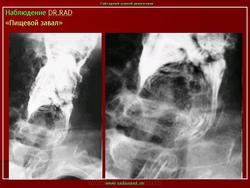

Интересно, а, что такое "пищевой завал"?

И.Бондаренко wrote:

"Пищевой завал" чаще наблюдается у лиц преклонного возраста, по статистике чаще у мужчин. В результате снижения тонуса пищеварительной трубки крупный пищевой кусок, чаще - мясо, просто застревает и обтурирует просвет пищеварительной трубки, чаще на уровне глотки, верхней части пищевода, но на много чаще на уровне 1 физиологического сужения - "рот Килиана".